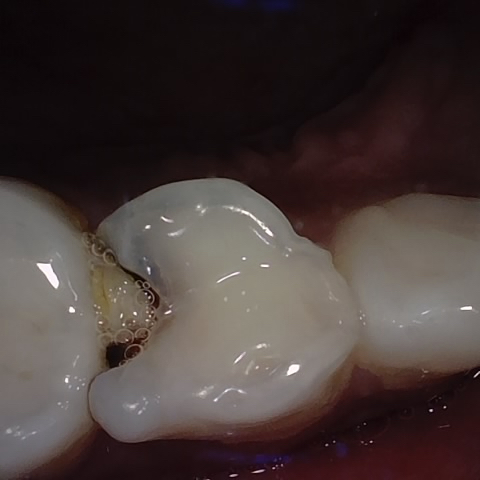

Annotated as "Good"